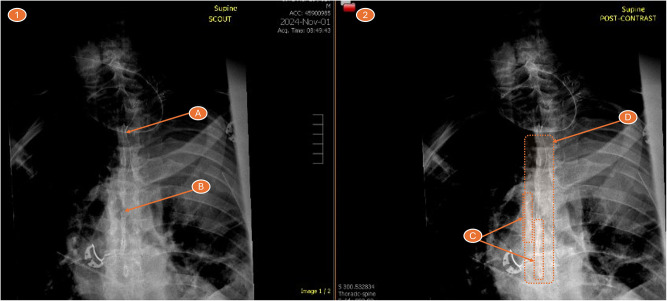

Epidural anesthetic techniques for postoperative analgesia are rarely considered in spinal surgery, and high thoracic epidural analgesia (TEA) is considered medically risky. We present a successful case of surgical retrograde placement of a thoracic (T6-T7) epidural catheter under direct surgical visualization via T2 laminectomy in a patient who underwent combined thoracotomy and spinal surgery. TEA was confirmed by epidurogram, provided adequate postoperative pain relief, and the patient was discharged home three days post-surgery.